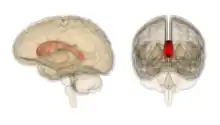

Corpus callosum

Coronal T2 (grey scale inverted) MRI of the brain at the level of the caudate nuclei emphasizing corpus callosum- Tractography of Corpus callosum

Corpus callosum with Anatomography